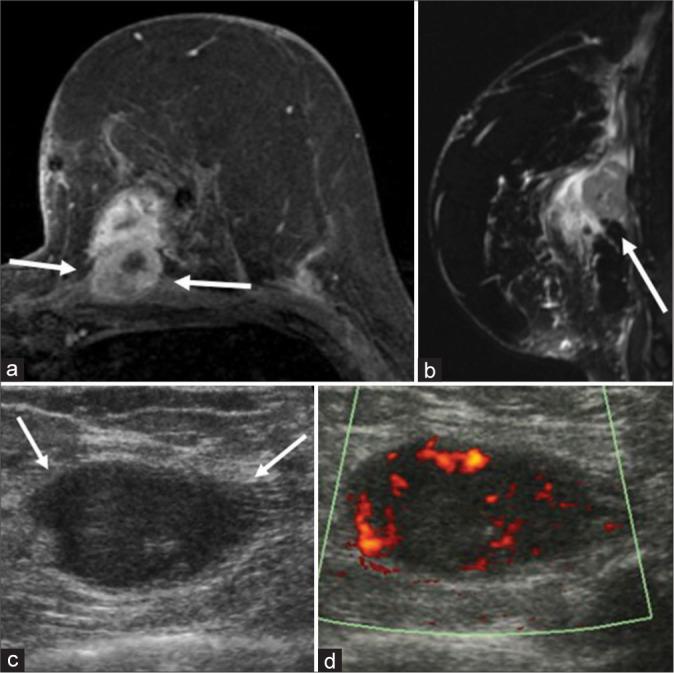

Of the 131 patients who met our inclusion criteria, 40 patients presented with breast cancer recurrence. The most common histopathologic type of primary breast cancer was invasive ductal carcinoma in 82.5% (33/40) of patients. Triple-negative breast cancer was the most common biological marker with 42.1% (16/38) of cases. Clinically, 70% (28/40) of the recurrences presented as palpable abnormalities. Of nine patients who underwent mammography, a mass was seen in eight patients. Of the 35 patients who underwent ultrasound evaluation, an irregular mass was found in 48.6% (17/35) of patients. Nine patients with recurrent breast cancer underwent breast MRI, and MRI showed an irregular enhancing mass in four patients, an oval mass in four patients, and skin and trabecular thickening in one patient. About 55% of patients with recurrent breast cancer were found to have distant metastases.

在符合我们纳入标准的131例患者中,40例出现乳腺癌复发。原发性乳腺癌最常见的组织病理学类型是浸润性导管癌,占患者的82.5%(33/40)。三阴性乳腺癌是最常见的生物学标志物,占病例的42.1%(16/38)。临床上,70%(28/40)的复发表现为可触及的异常。在接受乳腺钼靶检查的9例患者中,8例发现有肿块。在接受超声评估的35例患者中,48.6%(17/35)的患者发现有不规则肿块。9例复发性乳腺癌患者接受了乳腺MRI检查,MRI显示4例患者有不规则强化肿块,4例患者有椭圆形肿块,1例患者有皮肤和小梁增厚。约55%的复发性乳腺癌患者被发现有远处转移。